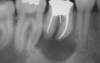

periapical abscess

periapical abscess